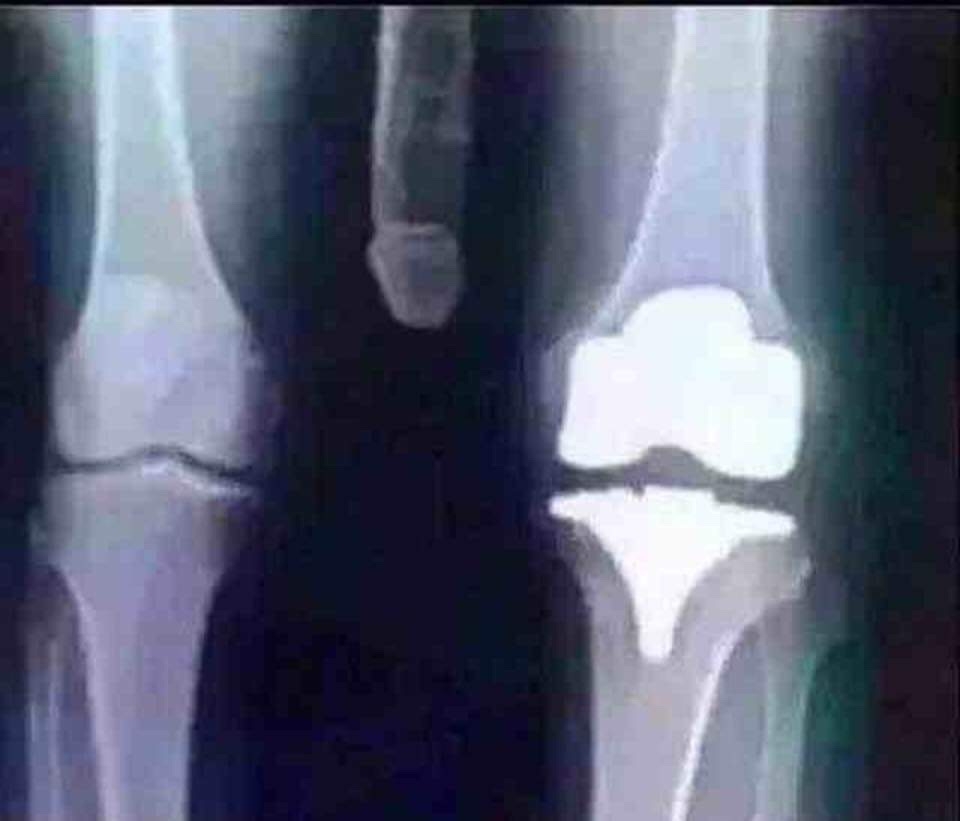

Knee! I've had both of mine done!

Since we're all sharing our x-rays I figured I'd share mine. I must say that PT was rough! I only did 8 weeks of it at home, and I never did any outpatient PT, so I do still have a lot of pain in the new knee. I've decided against doing the other knee, too painful!

knee

knee replacement thats the kneecap

Looks like the prosthetic component for the medial condyle of the femur and it’s quite possible that it’s part of a Total Knee Arthroplasty.

This is a partial knee joint replacement. I help put them in everyday except Friday Saturday and Sunday..Upper part.

This xray is revision surgery repair of snapped patellar tendon after total knee replacement. Recovery after this surgery required 8 weeks in a full leg cast (non weight bearing) miserable surgery, recovery and physical therapy!